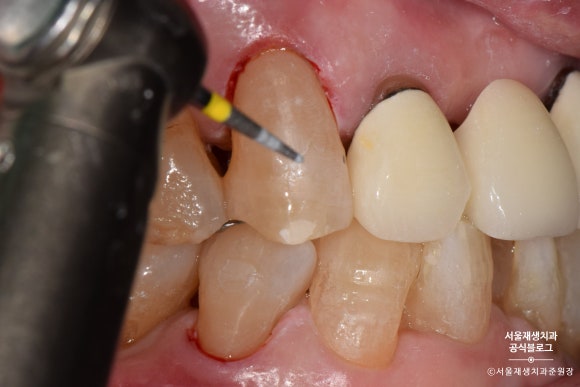

레진으로 치경부마모증 치료하기

레진은 글라스아이오노머에 비해

치료 과정이 복잡하고 술자의 손기술에 결과가 많이 좌우됩니다.

레진이 접착될 부위를 깨끗하게 소독하고

약제를 도포합니다.

레진을 치아에 접착시키는 약제를 도포합니다.

레진을 한 겹, 한 겹 정성껏 쌓아올립니다.

이때, 침이나 물 한방울도 튀지 않도록 조심!

들뜬 자리가 없도록 꼼꼼하게 레진을 다듬어줍니다.